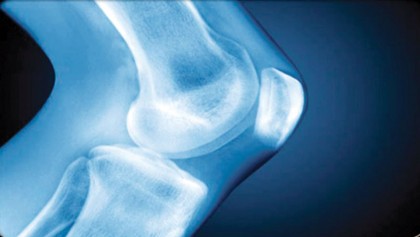

Osteoarthritis

Osteoarthritis is a form of arthritis that features the breakdown and eventual loss of the cartilage of one or more joints. Cartilage is a protein substance…